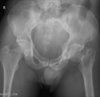

Normal hip xray

Anterior hip dislocation

126